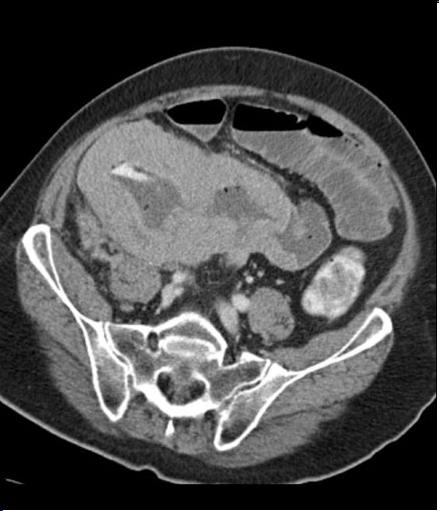

| Extension loco regionale

d'une lymphome T dans une maladie coeliaque de

l'intestin . ( la paroi de l'intestin dans ce cas

est perdre de villocite etendue ) . Image TDM ,

coupe frontale ( coronale ) |

Meme cas en PET /CT . Coupe

axiale . |